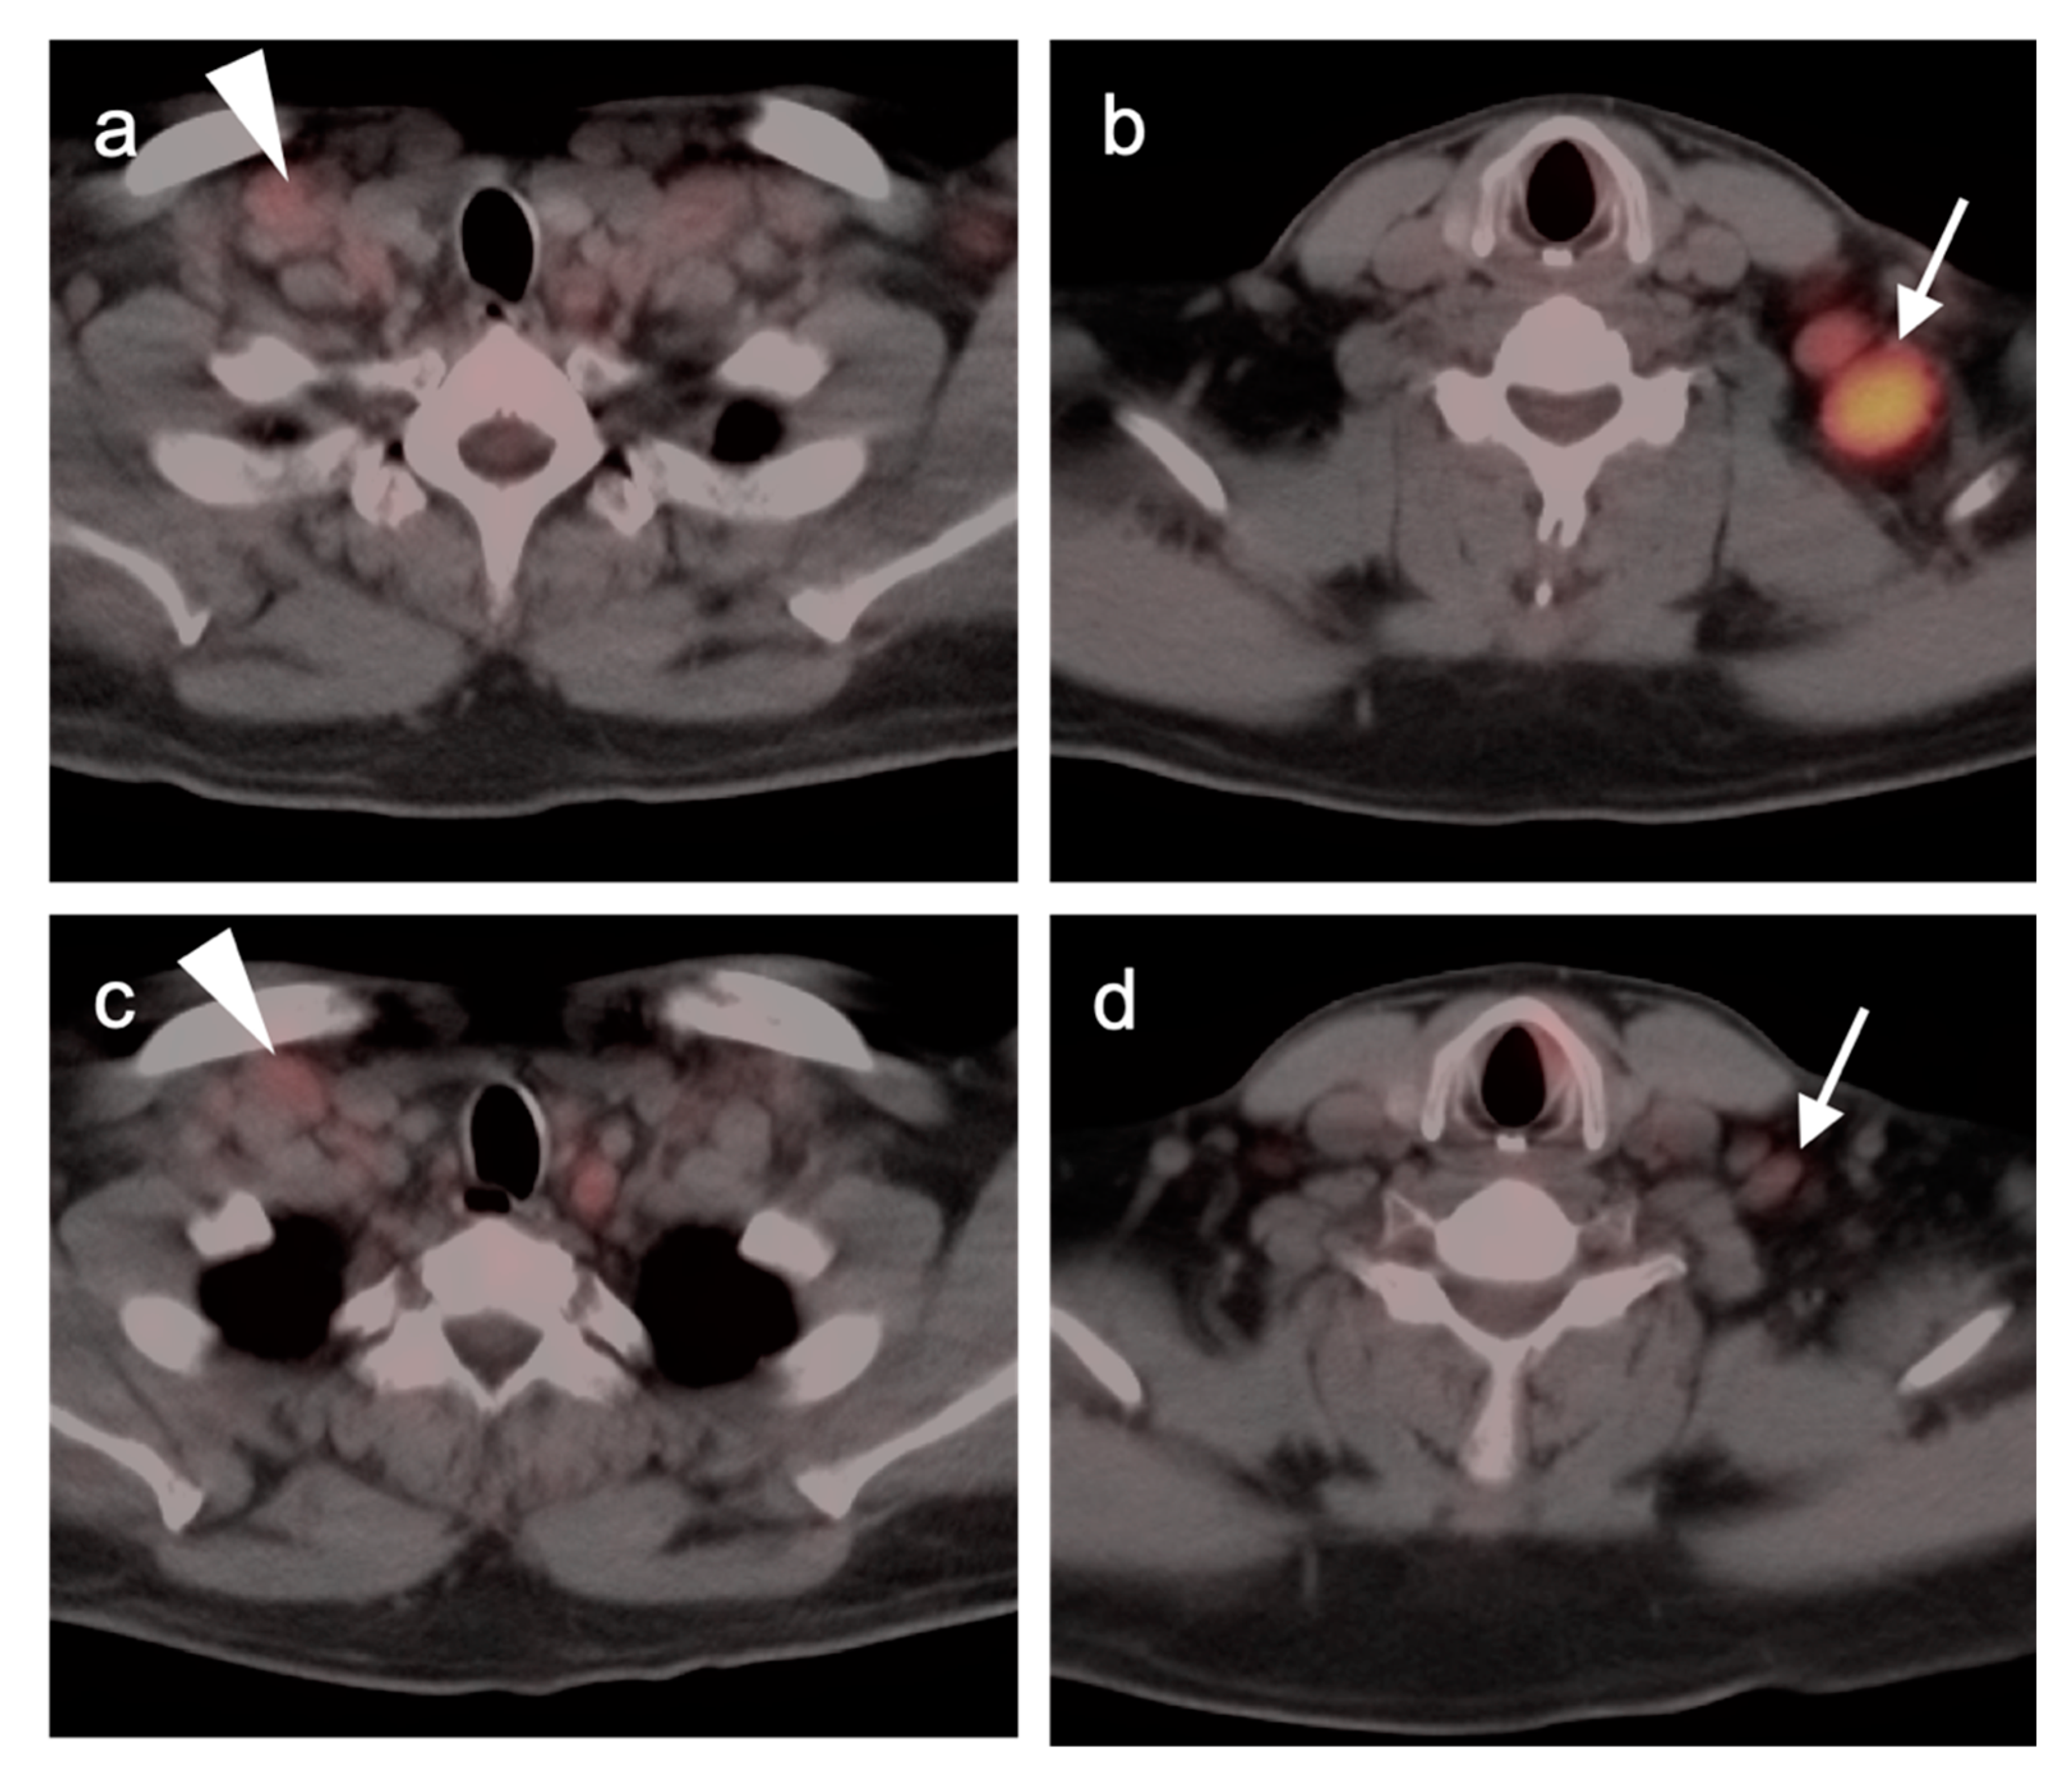

2.3.6. Multiple Myeloma (MM)

- Dimopoulos, M.; Terpos, E.; Comenzo, R.L.; Tosi, P.; Beksac, M.; Sezer, O.; Siegel, D.; Lokhorst, H.; Kumar, S.; Rajkumar, S.V.; et al. International myeloma working group consensus statement and guidelines regarding the current role of imaging techniques in the diagnosis and monitoring of multiple Myeloma. Leukemia 2009, 23, 1545–1556. [Google Scholar] [CrossRef]

- Lütje, S.; de Rooy, J.W.; Croockewit, S.; Koedam, E.; Oyen, W.J.; Raymakers, R.A. Role of radiography, MRI and FDG-PET/CT in diagnosing, staging and therapeutical evaluation of patients with multiple myeloma. Ann. Hematol. 2009, 88, 1161–1168. [Google Scholar] [CrossRef] [PubMed]

- Matteucci, F.; Paganelli, G.; Martinelli, G.; Cerchione, C. PET/CT in Multiple Myeloma: Beyond FDG. Front. Oncol. 2021, 10, 622501. [Google Scholar] [CrossRef]

- Agarwal, A.; Chirindel, A.; Shah, B.A.; Subramaniam, R.M. Evolving role of FDG PET/CT in multiple myeloma imaging and management. AJR Am. J. Roentgenol. 2013, 200, 884–890. [Google Scholar] [CrossRef]

- Michaud-Robert, A.V.; Zamagni, E.; Carlier, T.; Bailly, C.; Jamet, B.; Touzeau, C.; Moreau, P.; Kraeber-Bodere, F.; Nanni, C.; Bodet-Milin, C. Glucose Metabolism Quantified by SUVmax on Baseline FDG-PET/CT Predicts Survival in Newly Diagnosed Multiple Myeloma Patients: Combined Harmonized Analysis of Two Prospective Phase III Trials. Cancers 2020, 12, 2532. [Google Scholar] [CrossRef]

- Zamagni, E.; Nanni, C.; Dozza, L.; Carlier, T.; Bailly, C.; Tacchetti, P.; Versari, A.; Chauvie, S.; Gallamini, A.; Gamberi, B.; et al. Standardization of 18F-FDG-PET/CT According to Deauville Criteria for Metabolic Complete Response Definition in Newly Diagnosed Multiple Myeloma. J. Clin. Oncol. 2021, 39, 116–125. [Google Scholar] [CrossRef] [PubMed]